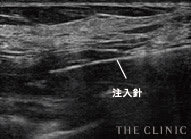

しこりを目視しながら丁寧に除去

アクアフィリング豊胸やアクアリフト豊胸のしこりは、触診だけの曖昧な見当で取り除けるものではありません。海外では「暗闇での手術」と危険視される行為です。

THE CLINIC ではアクアフィリング豊胸やアクアリフト豊胸後のしこりを確実に溶解・除去するため、必ず乳腺用エコーを使用。最短ルートでしこりを取り除けるので、体への負担を最小限に抑えます。

エコー下でしこりにアプローチし、確実に生理食塩水を注入 -